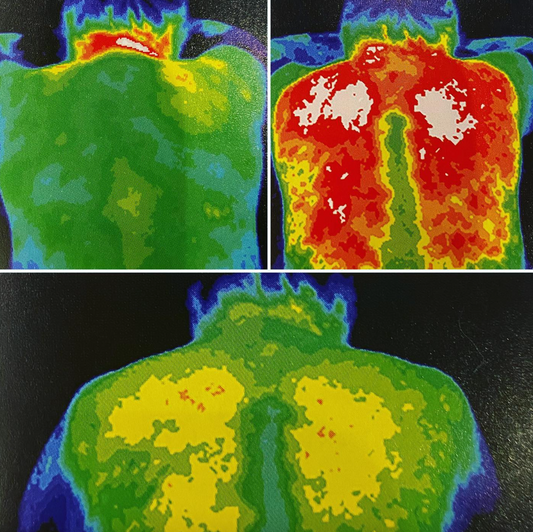

Thermographic imaging uses different colors to display the levels of activity in an area. The cooler the colors, the less circulation or activity is present in the region.Top left image:...